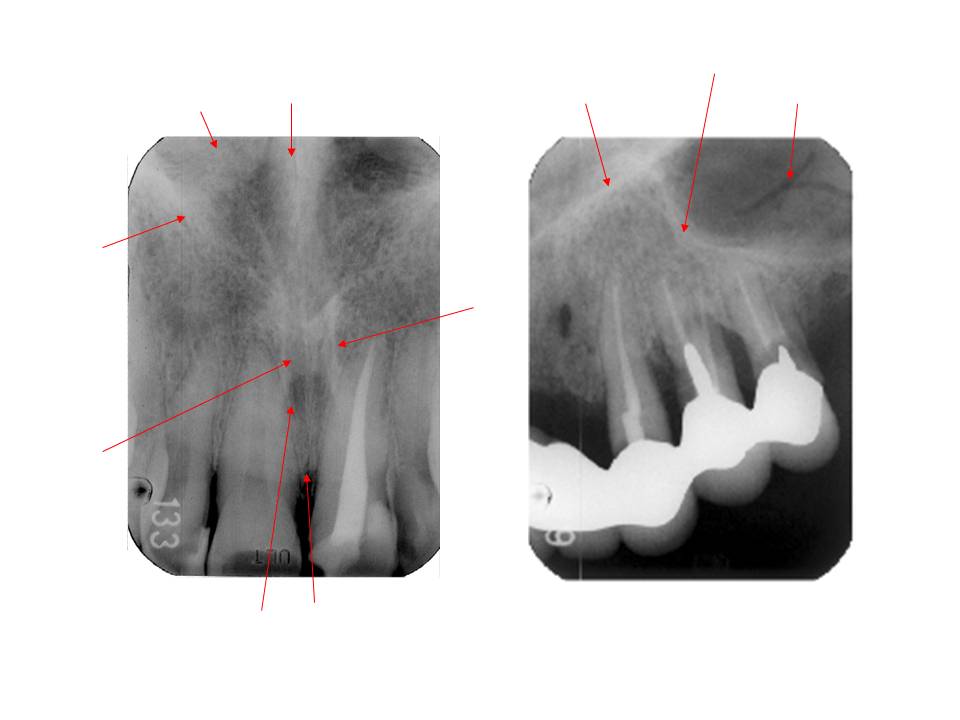

口内法(二等分法・咬合法)撮影の解剖